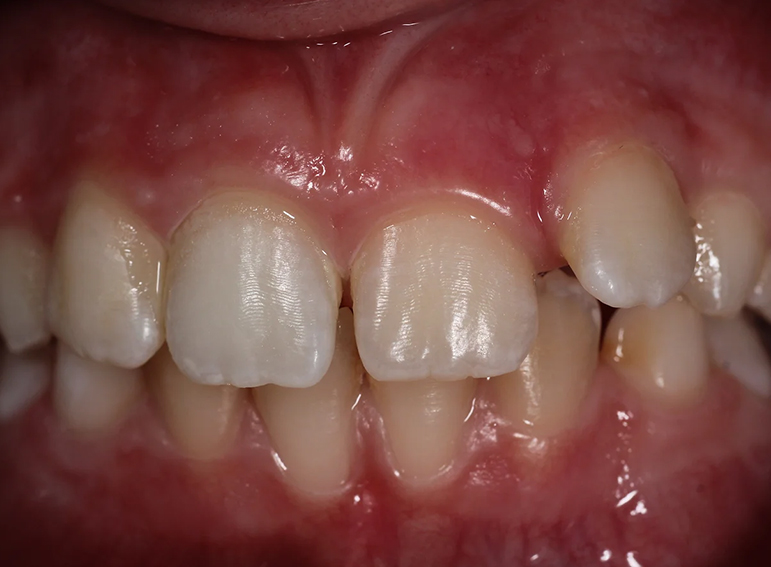

Case 1 – Children

Root filling of an immature tooth and bleaching.